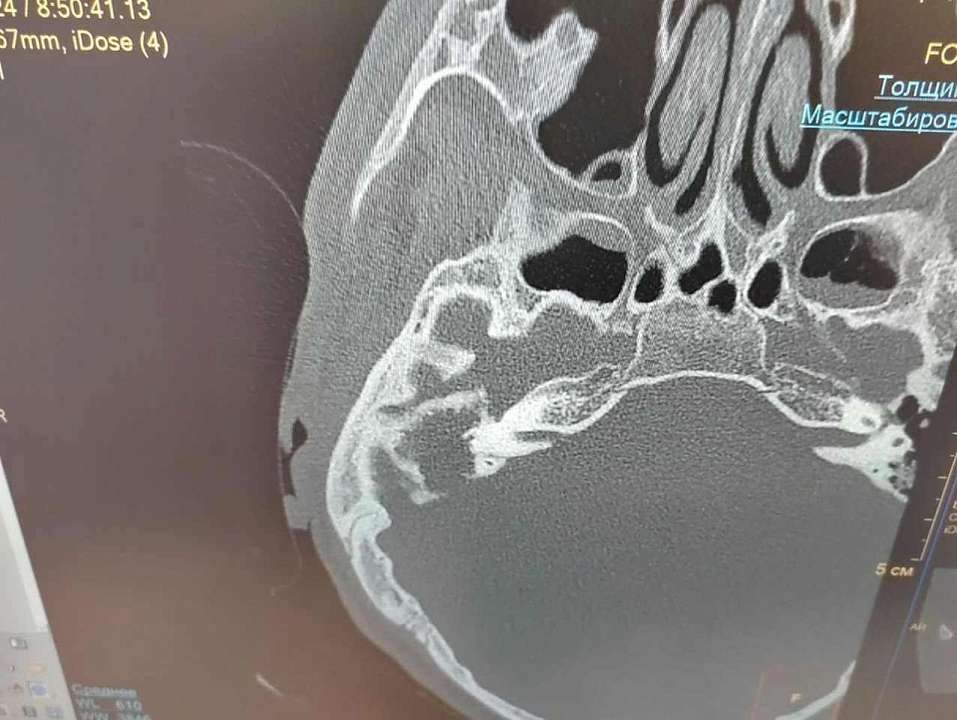

Медики определили, что у пациента есть признаки холестеатомы полостей среднего уха с признаками деструкции костной стенки сигмовидного синуса.

Санирующую операцию на правом ухе с тимпанопластикой и мастоидопластикой срочно провели врачи. Из полостей среднего уха удалили холестеатому. Бригада медиков также провела пластику костных дефектов.